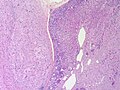

| Metastasis | sharp interface with brain, often glandular, +/-nucleoli, no glial processes | often cerebellular, well-circumscribed | usu. old | often suspected to have metastatic disease | TTF-1, CK7, CK20, BRST-2 |

- Well-demarcated border between brain and lesion - key feature.

- No cytoplasmic processes.

- Usu. have nuclear atypia of malignancy.

- Nuclei often ~3-4x the size of a RBC.

- +/-Glandular arrangement.

- +/-Nucleoli.